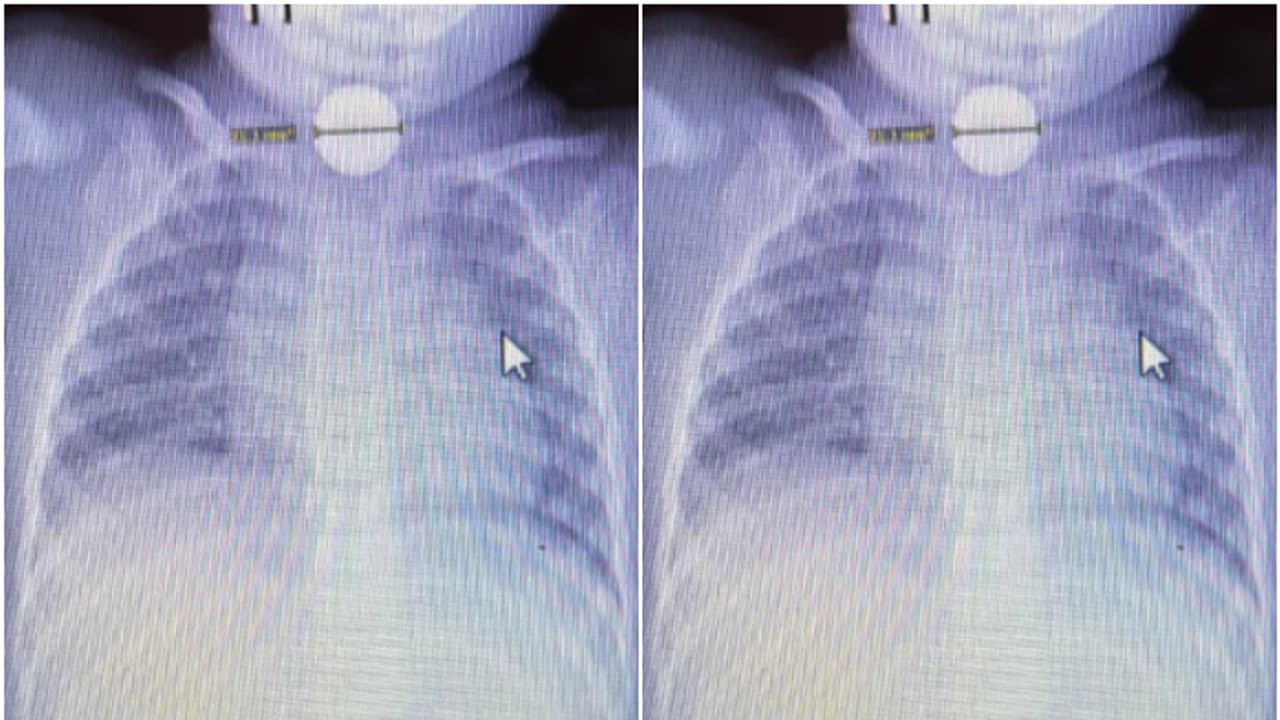

അമേരിക്കയിലെ ടെക്സസിലാണ് സംഭവം. കടുത്ത വയറുവേദനയെ തുടര്ന്ന് കുഞ്ഞ് നിലവിളിച്ചതോടെയാണ് അമ്മയായ മഡലൈന് ഡൺ കുഞ്ഞിനെ ഉടൻ തന്നെ ആശുപത്രിയിലെത്തിച്ചത്. രാത്രി 11 മണിയോടെയാണ് കൈ എന്ന കുഞ്ഞ് ഉണര്ന്ന് നിലവിളിച്ചത്. അസഹനീയമായ വേദന കൊണ്ട് പുളഞ്ഞ കുഞ്ഞിനെ ആശുപത്രിയിലെത്തിച്ചപ്പോള് ആദ്യം വയറ്റില് വൈറസ് ബാധയാണെന്നാണ് ഡോക്ടര്മാര് കരുതിയത്. കുഞ്ഞ് എന്തോ വിഴുങ്ങിയെന്ന സംശയം ഉള്ളതിനാല് അമ്മയുടെ അഭ്യര്ത്ഥന പ്രകാരം ഡോക്ടര്മാര് എക്സ്റേ എടുത്തു. ഇതോടെയാണ് ബട്ടൺ ബാറ്ററി കുഞ്ഞ് വിഴുങ്ങിയതായി കണ്ടെത്തിയത്. പെട്ടെന്ന് തന്നെ ഡോക്ടര്മാര് അടിയന്തര ശസ്ത്രക്രിയ നിര്ദ്ദേശിക്കുകയായിരുന്നു. കുഞ്ഞിനെ അടിയന്തര ശസ്ത്രക്രിയക്ക് വിധേയനാക്കുകയുമായിരുന്നു.